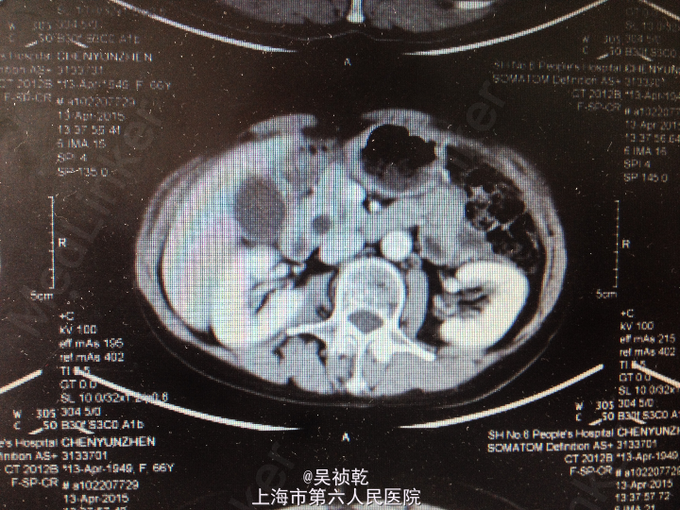

查体:皮肤巩膜无明显黄染,腹部平坦,未见明显胃肠型及异常隆起,全腹软,右上腹部压痛不明显,无反跳痛,无肌卫,无腹部反跳痛,全腹无包块,肝脏肋下未触及,脾脏肋下未触及,无肝区叩击痛,Murphy’s征阴性,肠鸣音正常,移动性浊音-。 辅查:血常规(2015-4-1):WBC:5.9×109/L,N:57.6%,RBC:4.17×1012/L,Hb:127g/L,PLT:196×109/L。肝功能:ALT:109U/L,AST:87U/L,TB:18.6umol/L。肿瘤标记物:AFP:2.7ug/L,CEA:4.71ug/L,CA19-9:37.19KU/L。 2015-4-13 上腹部MRI报告:1.胆总管下段异常信号,胆总管、胰管轻度扩张,胆总管下段结石可能大,必要时MRI增强检查,排除胆总管下段占位。2.胆囊颈结石,胆囊增大。3.附见;肝脏左叶囊性病灶。 2015-4-14上腹部增强CT报告:1.胆总管下端异常强化,结石可能,肝内外胆管及主胰管扩张,胆囊增大,必要时MRI增强进一步检查。2.肝脏小囊肿。

1. 患者入院后于4.13无明显诱因下出现右上腹疼痛,压痛明显,拒按。结合腹部CT及MRI影像学表现,胰胆管明显扩张,考虑急性胰腺炎发作。辅查:2015-4-14 生化检验报告:淀粉酶(干式) 1640 U/L ↑。生化检验报告:总蛋白 61 g/L ,白蛋白 36 g/L ,白/球比例 1.4 ,谷丙转氨酶 218 U/L ↑,谷草转氨酶 183 U/L ↑,γ-谷氨酰酶 548 U/L ↑,总胆红素 13.3 μmol/L ,直接胆红素 5.4 μmol/L ,肌酐 66 μmol/L ,血清钾 4.3 mmol/L ,血清钠 142 mmol/L ,血清氯 106 mmol/L ↑。门诊化验检验报告:白细胞 6.3 *10^9/L ,红细胞 3.84 X10^12/L ,血红蛋白 117 g/L ,细胞比积 35.9 % ,血小板 197 X10^9/L ,中性细胞百分比 58.7 % 。甲胎蛋白(AFP) 2.68 ng/mL ,癌胚抗原(CEA) 4.99 ng/mL ,糖类抗原(CA125) 6.91 U/mL ,糖类抗原(CA199) 39.45 U/mL ↑。处理:予禁食,查血、尿淀粉酶,抑酸、保肝、补液支持治疗,经治疗后症状缓解。 2. 因患者无黄疸,为进一步明确胆总管梗阻原因,4.16 行ERCP+ERBD+十二指肠乳头活检术。 检查治疗经过:十二指肠镜进入十二指肠,降部内侧见乳头,十二指肠乳头肿大,粘膜面外观正常,触之易出血。BOSTON-Jagwire导丝留置胰管,BOSTON-Jagwire导丝进入胆管引导COOK-FS-OMNI导管造影,胆管显影,胆管扩张,胰管造影胰管扩张。胆管胰管内未见充盈缺损。十二指肠乳头开口处取四块活检。放置辛菖猪胆道引流管(8.5F,6cm),辛菖胰管引流(F5,4cm),引流畅。结合MRI及CT考虑壶腹部占位可能。十二指肠乳头活检病理:绒毛状腺瘤伴部分腺体重度不典型增生,局灶癌变。 3. 患者术前诊断为十二指肠壶腹部癌,于4.23 行剖腹探查,胰十二指肠切除术。术中见:见腹腔内无腹水,腹膜、盆腔内、大网膜、肝脏、肝十二指肠韧带、胰腺周围、腹腔动脉周围、肠系膜根部、腹主动脉旁等无转移性结节和肿大淋巴结。探查见此患者左右肝胆管的汇合处接近胆胰管汇合处,右侧肝胆管壁水肿增粗,十二指肠乳头部肿块大小0.3cm,行胰十二指肠完整切除。 4. 术后病理检查报告:下半胃、胰腺、十二指肠;标本类型:切除胰腺大小 4×4×1 CM,十二指肠长 15CM,胃小弯长 8 CM,大弯长 11CM,胆囊9×3×1.5CM;肿瘤部位:肿瘤位于十二指肠乳头,大小0.5×0.3CM;组织学类型内容: 腺癌II级;血管浸润(-),淋巴管浸润(-),神经周围浸润(-);切缘: 上、下切缘及胰腺切缘均未见癌;淋巴结:以下淋巴结均未见癌转移:胰腺旁LN:0/8枚,胃大弯LN:0/6枚,胃小弯LN:0/3枚。;淋巴结免疫反应状态: SH(+), PH(+), GH(+);肿瘤旁病变: 粘膜组织慢性炎(十二指肠乳头):腺癌II级,肿瘤侵及肌层,未累及胰腺,胰腺导管扩张,小胆管增生伴中度不典型增生。(胆囊):慢性胆囊炎伴腺体增生。肿瘤组织免疫酶标记结果:CA199(-)、CEA(+)、S-100(-)、CK19(+)、CK7(+)、CDX2(-)、CK(-)、Ki67(80%+)。